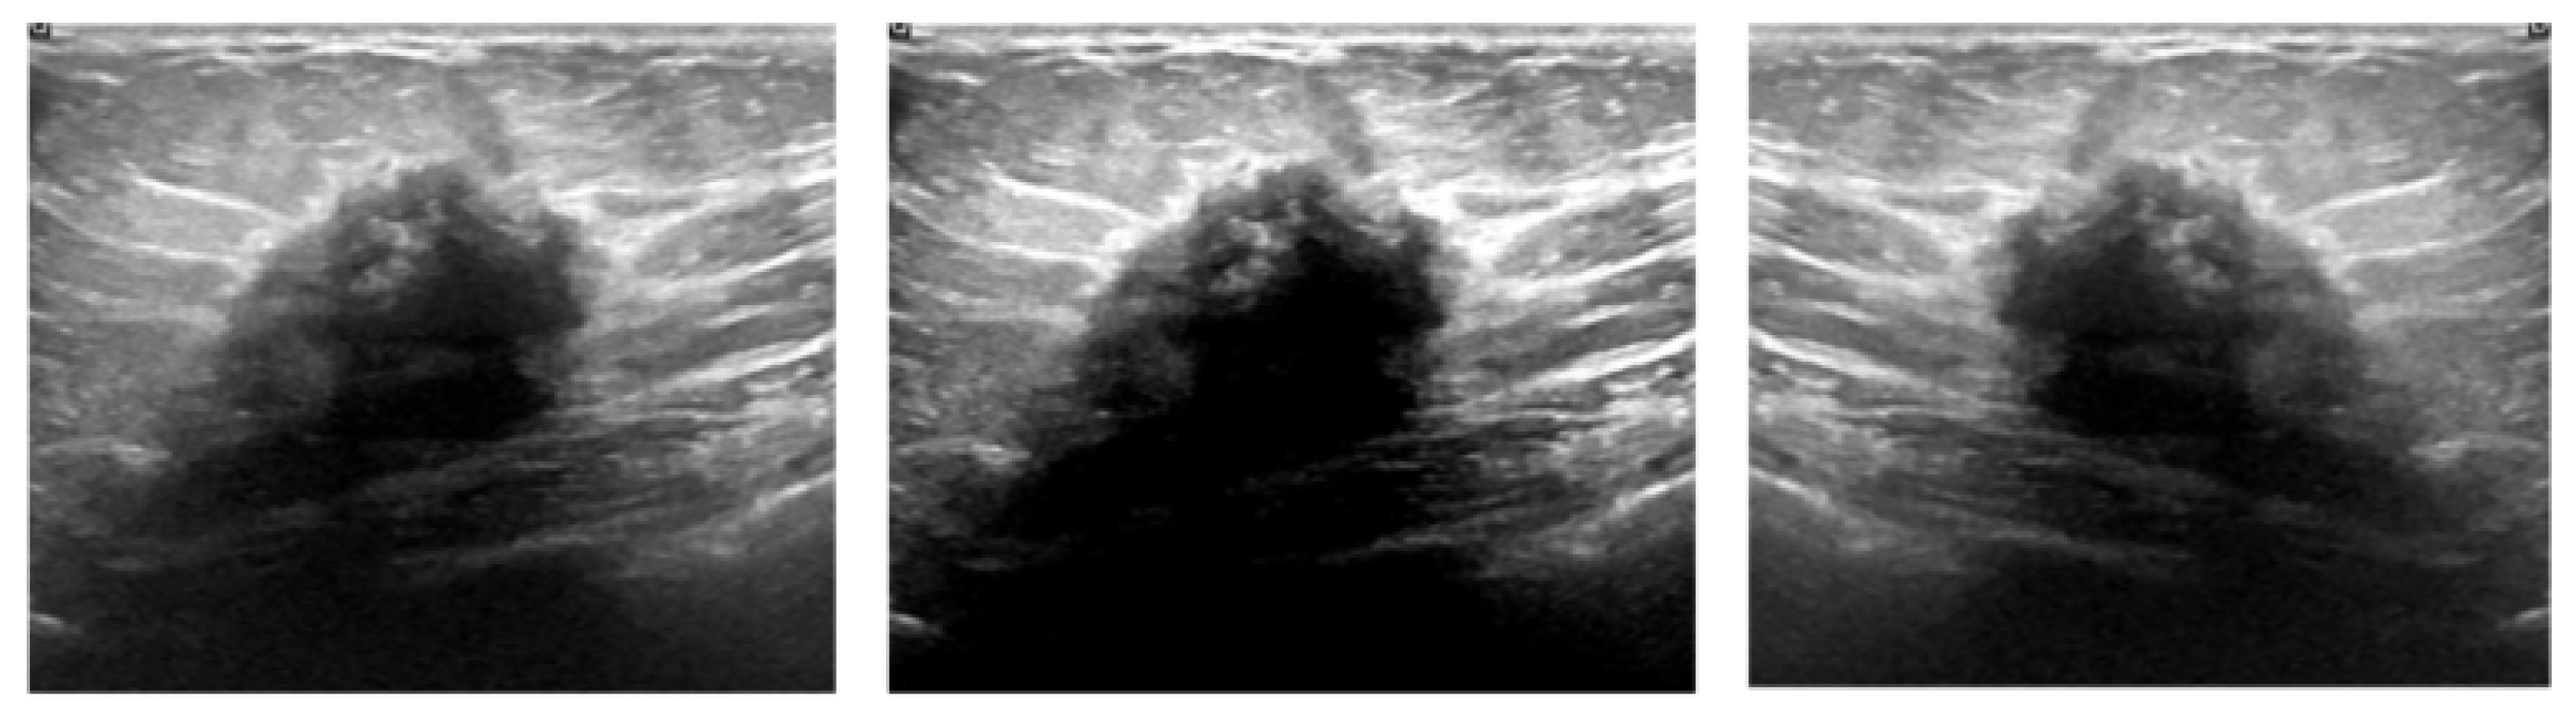

4.1. Dataset and Preprocessing